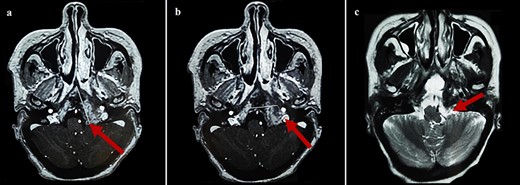

By the end of biological exploration, the patient reported a recurrence of headaches and blurred vision, 2 months after surgical decompression. Cerebral MRI revealed a relapse of the sphenoid plasmacytoma, measuring 70 mm (Fig. 3). Given the pathological diagnostic result, surgical re-intervention was not decided. Instead, the patient was treated with external beam radiotherapy (RTX) focused on the sphenoid bone (30 Gy), followed by immunochemotherapy with zoledronic acid. After 6 months, complete response was noted with the resolution of symptoms, disappearance of the monoclonal band, normalization of sFLC, and persistence of lytic sequelae on cerebral MRI (Fig. 4). Autologous stem cell transplantation (ASCT) was successfully performed, and the patient was put under treatment maintenance. After 18 months of follow-up, clinical, biological, and radiological evaluation confirmed sustained complete remission.

Cerebral MRI (axial views) showing a relapse of the sphenoid BP measuring 70 mm (a, b: T1 weighted post-gadolinium; c: T2 weighted).